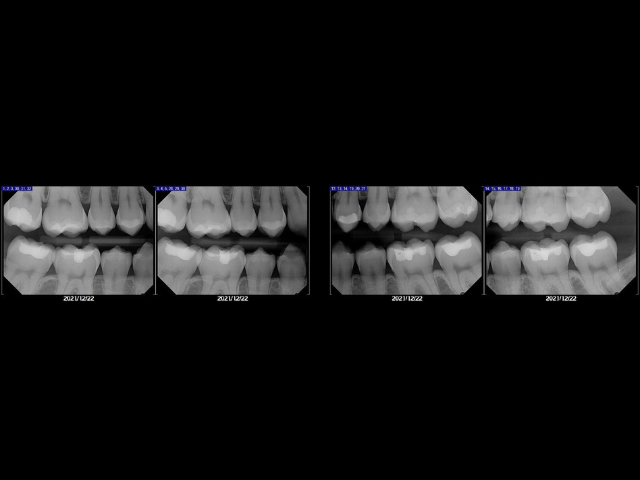

Healthy teeth and gums start with clear information. Bitewings and digital X-rays give dentists a detailed look at areas that cannot be seen with the eyes alone. These images help prevent small problems from becoming bigger issues and guide the dentist in creating the best plan for each patient. When patients receive bitewings and digital X-rays at Brady Dental Group in Amarillo, Texas, they benefit from advanced technology, gentle techniques, and a deeper understanding of their own oral health.

Many patients are surprised at how fast and comfortable digital X-rays are. The process is simple and the results appear instantly on the screen. This makes it easy for the dentist and patient to review everything together. Often, the images reveal cavities in between the teeth and help the dentist make a better diagnosis for the patients long-term dental care.

Bitewings are a type of digital X-ray used to examine the upper and lower teeth at the same time. They help identify cavities between teeth, changes in bone levels, and the condition of existing fillings. Since bitewing images capture the areas where decay most often develops, due to inadequate flossing and harder to reach areas, these xray’s are an essential part of routine dental checkups.

Digital X-rays, including bitewings, produce clear and detailed images that can be adjusted on the computer. This makes it easier to spot early signs of decay or gum disease. It also helps the dentist track changes over time and compare images from previous visits.

At Brady Dental Group in Amarillo, Texas, the digital X-ray system uses very low radiation and offers a level of clarity that older film X-rays cannot match. The images help the dentist make informed decisions and help patients feel confident in their care.

Bitewings reveal hidden problems early. Most cavities begin between the teeth, where toothbrush bristles cannot reach. Without bitewing images, these cavities would continue to grow unnoticed until they cause pain or require more complex treatment.

By catching these issues early, the dentist can treat them quickly and help the patient avoid discomfort and expense. This is one reason bitewings are typically recommended once a year.